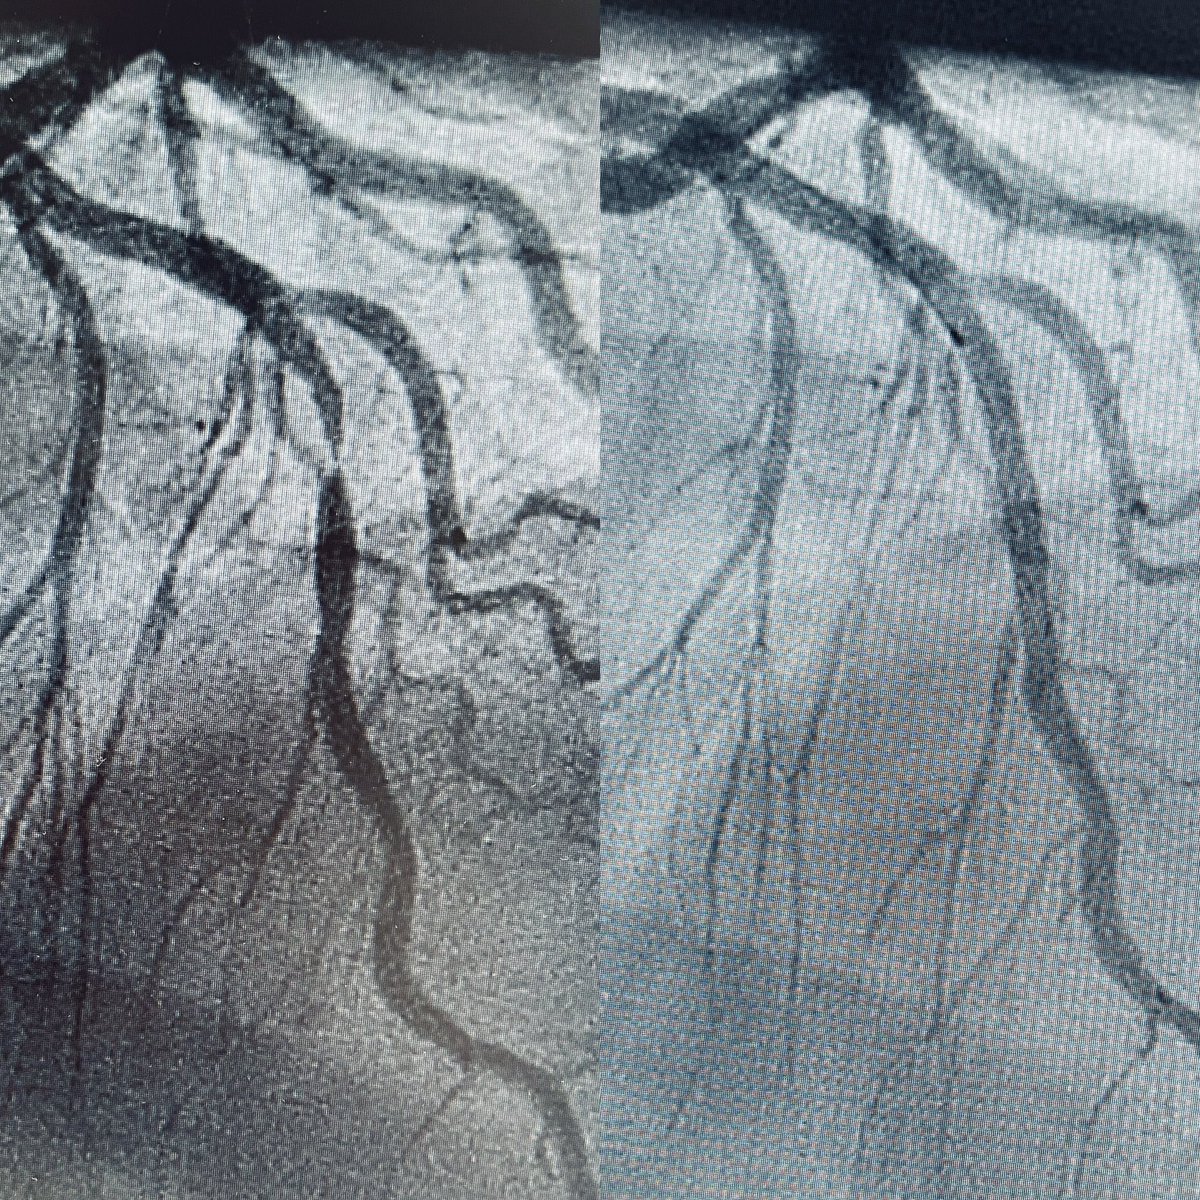

NSTEMI due to subtotal 1:1:1 LM Bifurcation stenosis. Cut & crack (Wolverine & OPN): stent LM to LAD, drug coated balloon ostial LCX! Planned angiographic follow up at 9 months. What are your thoughts?